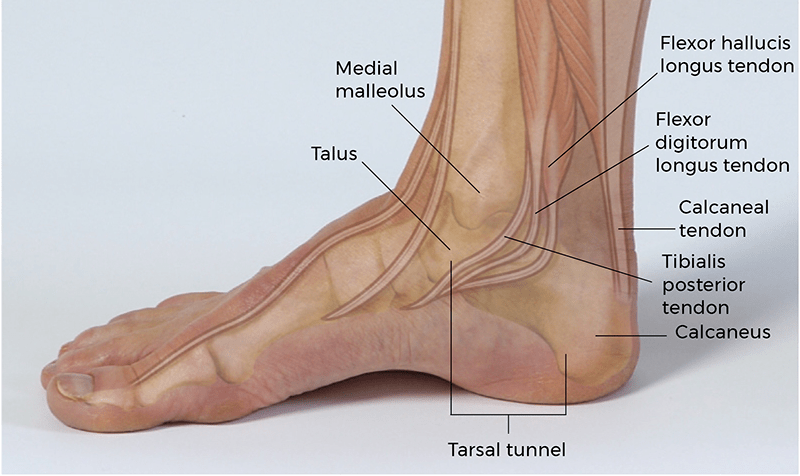

The tarsal tunnel is an anatomical structure located on the medial side of the ankle where the foot joins the lower leg. Specifically, it is located posterior and inferior to the medial malleolus. Unlike the carpal tunnel of the wrist, which is oriented horizontally and has an osseous floor and fibrous roof, the tarsal tunnel is oriented vertically. The osseous lateral portion of the tunnel is formed by the medial malleolus anteroposteriorly and the posterior talus and calcaneus bones laterally. A fibrous flexor retinaculum extending from the medial malleolus to the medial calcaneus forms the medial border of the tarsal tunnel. This structure holds the contents of the tarsal tunnel up against the bone, preventing medial displacement.

Similar to the carpal tunnel of the wrist, the tarsal tunnel serves as an important passageway for several structures. These include the tendons of the tibialis posterior, flexor digitorum longus (FDL), and flexor hallucis longus (FHL). Running alongside these three tendons are the posterior tibial nerve, artery, and vein. Organized from medial to lateral, the contents of the tarsal tunnel are the tibialis posterior tendon, FDL tendon, posterior tibial artery and vein, posterior tibial nerve, and FHL tendon. The posterior tibial nerve bifurcates within the tarsal tunnel (most common) or just proximal to it (less common) into the medial and lateral plantar nerves.